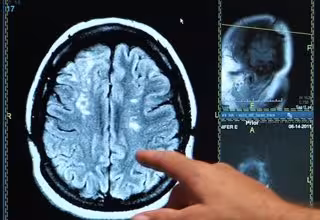

Investigadores identifican una proteína cerebral crucial para la recuperación tras un derrame cerebral

Ictus, derrame cerebral, cerebro

Una investigación de la Facultad de Medicina de la Universidad de Pittsburgh (Estados Unidos) ha identificado una proteína cerebral, llamada 'UCHL1', que puede ser clave para la reparación de las células nerviosas después del daño por accidente cerebrovascular. El estudio, realizado en modelos animales, evidencia que esta proteína podría ser un objetivo factible para desarrollar fármacos que ayuden a mejorar la recuperación.